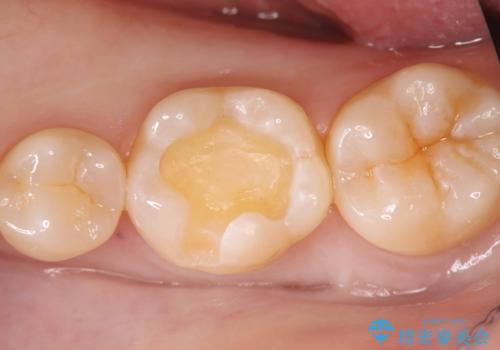

歯が欠けたことによるものか、もしくは以前装着された修復物の不適合が原因と考えられますが、銀歯(メタルインレー)と歯との間に大きな段差が認められ、汚れが溜まりやすい状態となっていました。

このような状態では、修復物の内部で虫歯が進行している可能性が高いため、治療が必要と判断しました。

今回は、経年的な劣化が少なく、汚れが付着しにくいセラミックインレーを用いて治療を行いました。